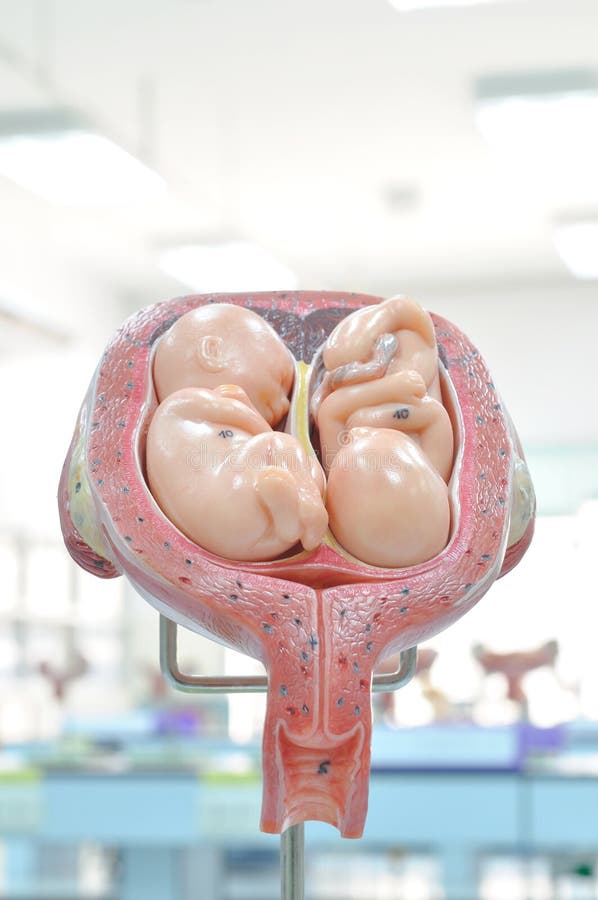

Анатомия женского организма: строение и функции матки

Раздел: Фотопуть к знанию